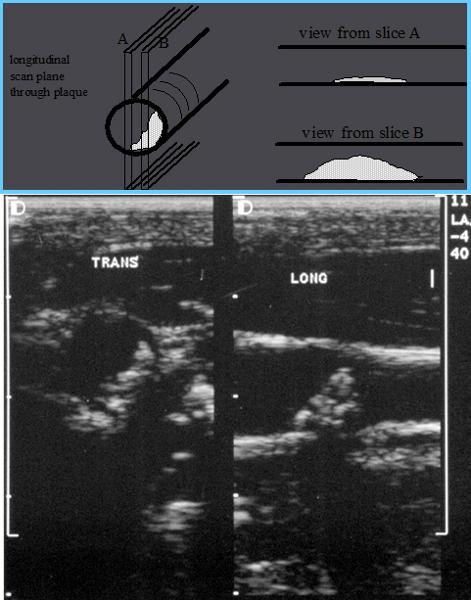

How should plaque be measured?

transverse measurement

lumen vs true lumen

Why is plaque measured in transverse?

Longitudinal estimation of stenosis from B-mode image is usually unreliable, use transverse image.

*This minor plaque can be made to appear more or less stenotic in longitudinal view